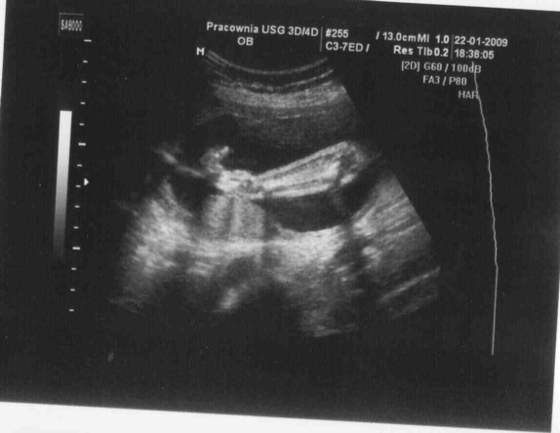

ja tez pochwale sie wam moja niunia, a poniewaz nie wklejalam wczesniejszych zdjęć to wkleje teraz kilka z 8 tygodnia, 14, 22

didi twoja corcia ma nozke pokazna, a moja raczke tez niczego sobie ;-)